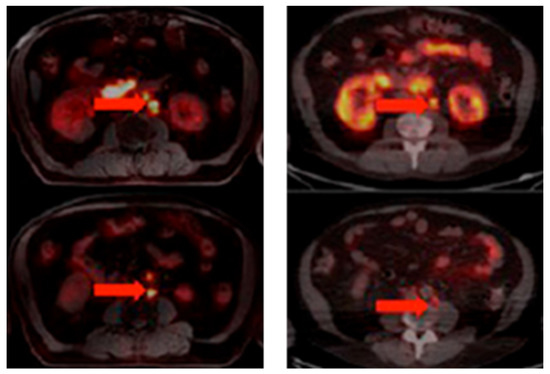

The development of PCa-specific imaging agents evolved rapidly. One particular group of tracers with the potential for PCa detection is that of the bombesin receptor antagonists, which target the GRPR. Despite the lower overall proportion of PCa exhibiting GRPR expression versus PSMA, the overexpression of GRPR is already found in primary tumors, while PSMA expression increases with PCa progression [120,121]. The bombesin receptor antagonist [68Ga]Ga-RM2 revealed PET/CT scan results that were similar to those using [68Ga]Ga-PSMA-11 in a small group of PCa patients (Figure 8) [122]. Moreover, compared with [68Ga]Ga-PSMA-11 (which accumulated in the salivary glands, lacrimal glands, and small intestine), the physiological uptake of [68Ga]Ga-RM2 was limited to the pancreas. [68Ga]Ga-RM2 could also provide more information about the retroperitoneal lymph nodes than the PSMA-targeted tracer. GRPR-targeted imaging agents may be a supplementary tracer for PSMA-negative patients.

Figure 8. [68Ga]Ga-RM2 (left) vs. [68Ga]Ga-PSMA-11 (right) PET/CT images of PCa lesions (red arrows) in a patient with LNM. This research was originally published in the Journal of Nuclear Medicine (JNM) [122].